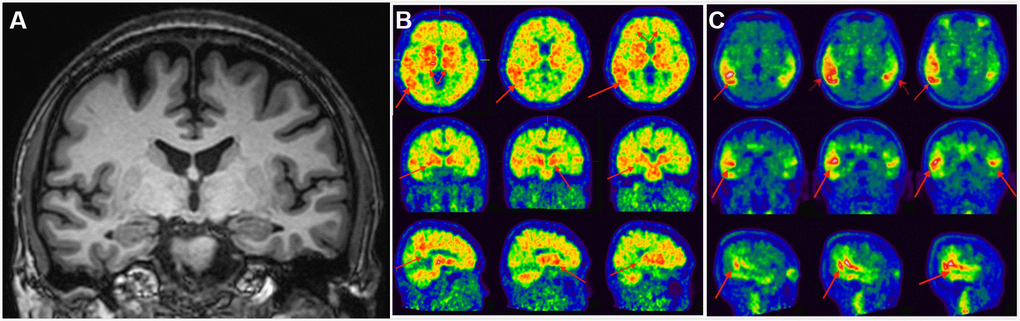

In this study, sensitivity of visual MTA rating in detecting AD at an early stage was low, which might partly be explained by the fact that the current visual grading has a floor effect (Figure 2). However, devising a finer visual scale may be challenging as detecting small volumetric change by human vision may not be possible and is also not reliable. The intra-rater reliability of this study obtained from an experienced neuroradiologist was 0.74 (weighted Kappa), which was compatible with that obtained from study among experienced neuroradiologist [25]. However, among general radiologists, the intra-rater reliability could be as low as 0.38 [25]. As a whole, if a finer visual scale is used, the reliability will likely be even lower. Note that the current machined-based automated tool had a test/re-test precision of 100%.

Figure 2. Clinical utility of AD-RAI in MCI subjects. A 50-year-old man with 16-year education had complaints of impaired short-term memory for 4 years. Z-score in Trial 4 of HKLLT was -2.97 SD (≤ -1 SD, i.e. MCI). The average visual MTA rating score was 0 suggestive of non-AD (A). HV measures also suggested non-AD, with a normal raw HV of 7.25mL (> 6.07mL) and HF of 0.48% (> 0.41%). However, AD-RAI was 0.68 (> 0.5) suggestive of AD. Subsequent PIB PET (B) and T807 PET (C) confirmed PIB and T807 retention, respectively (red arrows). The final diagnosis of this subject was prodromal AD. Abbreviations: AD-RAI=Alzheimer’s disease resemblance atrophy index; MCI=mild cognitive impairment; MTA=medial temporal lobe atrophy; HKLLT=Hong Kong List Learning Test; SD=standard deviation; MRI=magnetic resonance imaging; HV=hippocampal volume; HF=hippocampus fraction; PET=positron emission tomography; SVD=small vessel disease.